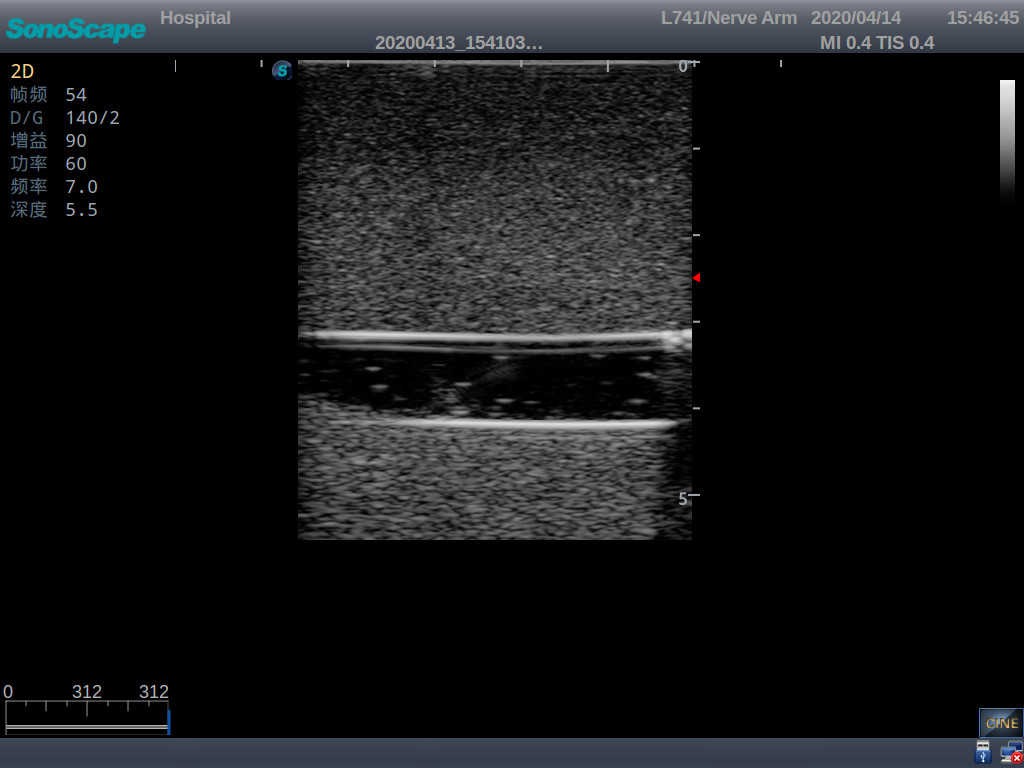

1)   Made of high molecular polymer ultrasound material, close to the real skin

2)   It can be used by real ultrasound machines

3)   Clear and real images of the tissues and organs (basilic vein and superior vena cava)